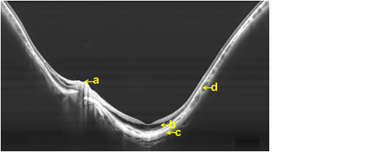

Широкопольные сканы SS OCT в два раза превышают размерами максимально широкие сканы SD OCT и в сочетании с глубиной сканирования позволяют визуализировать задний полюс глаза у пациентов с высокой миопией по всей ширине скана.